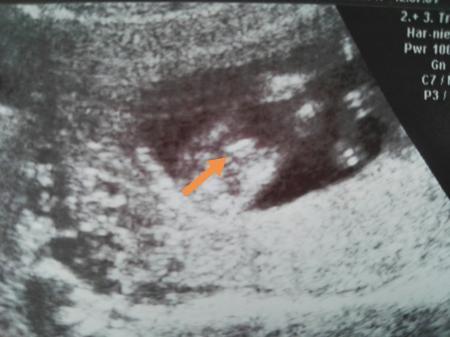

Also hier ist es nochmal deutlicher . Danke für eure Tipps. Ich weiss es ist schwer in der 12 sww.

Bild zu

Finde es sieht nach schamlippen aus. Aber 12. Woche ist verspannt schwer eine gute Aussage zu machen, auch für Ärzte!

Dankeschön für eure Antwort. Ja manche finden es unverschämt or sind entsetzt .Aber alles gut ,kann damit um gehen .Ja hatte beim 2 Foto ein Pfeil gemacht .Aber mal schauen was es wird am 07.03 weiss ich Bescheid